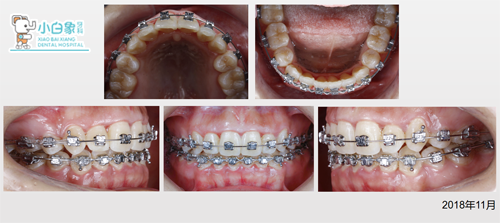

治疗中